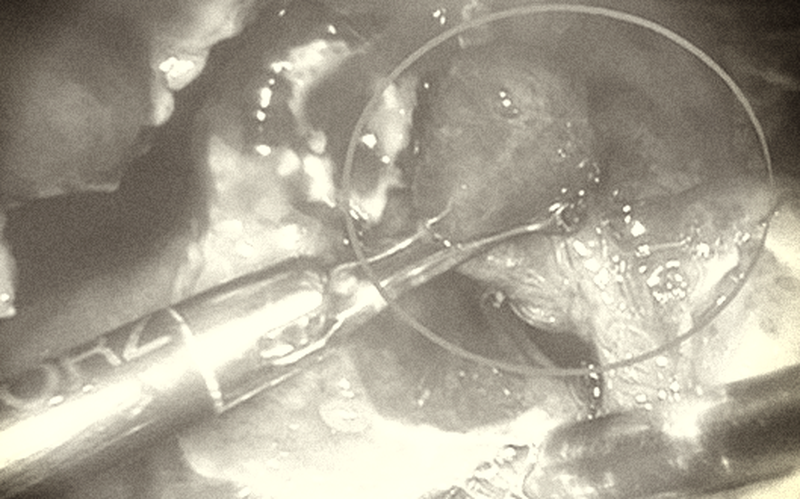

Sau khi tiếp nhận, thăm khám và làm các xét nghiệm, các bác sĩ xác định bệnh nhi bị viêm ruột thừa giai đoạn muộn, ruột thừa đã vỡ, gây viêm nhiễm lan tràn trong ổ bụng, phải mổ cấp cứu. Rất may mắn là các bác sĩ đã phẫu thuật được cho bệnh nhi bằng phương pháp nội soi, gỡ dính, cắt ruột thừa, hút rửa hết mủ trong ổ bụng.

Bệnh nhi được chẩn đoán viêm phúc mạc ruột thừa trong ổ bụng do ruột thừa đã vỡ, dịch mủ toàn bộ ổ bụng, được tiến hành phẫu thuật cấp cứu nội soi cắt ruột thừa viêm, rửa sạch ổ bụng, đặt dẫn lưu ổ bụng.